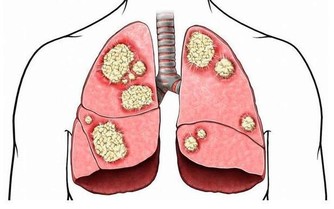

有時候指甲的形狀會出現2種改變方式,一種是指甲呈現扁圓狀改變,另一種則呈現半圓形改變。如果你的指甲扁圓形改變,說明你的腸味淤積的毒素過多,可能還伴有慢性腸炎、消化不良等腸胃疾病。一般此類病人還會有營養代謝障礙,這樣一來就會影響其他臟器的正常運行,特別是對肺部的影響較大。

大便不通,毒素不能及時排出體外,而被機體重新吸收,造成人體中毒,引發多種疾病。如毒進入血液,損害血管,氣血運行障礙,日久可導致動脈硬化、高血壓、高血糖、高脂血症、冠心病、腦梗死等心腦血管疾病。

毒被皮膚吸收,可發生痤瘡、牛皮癬等皮膚病。毒素存留體內,使氣血運行障礙,正常流通受阻,使臟腑得不到正常濡養,導致臟腑功能失調,從而更加重了毒素在體內的存留,加重對機體的破壞,導致衰老。